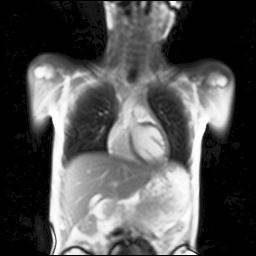

Refer to captionRefer to captionRefer to captionRefer to captionRefer to captionRefer to captionRefer to captionRefer to captionRefer to captionRefer to captionRefer to captionRefer to captionRefer to captionRefer to caption

Figure 5: Maximum inspiration (top row) and maximum expiration (bottom row) for different slice positions of one patient from back to front.

For a complete chest volume coverage, the lung is scanned at different slice positions as shown in Figure 5. At each slice position, a dynamic 2D+t image series with 140 images is acquired. For the further analysis of the image data, all images of one slice position need to be spatially aligned. We choose the image which is closest to the mean respiratory cycle as fixed image of the series. The other images of the series are then registered to this image. Our data set consists of 48 lung acquisitions of 42 different patients. Each lung scan contains between 7 and 14 slices. We used the data of 34 patients for the training set, 4 for the evaluation set, and 4 for the test set.